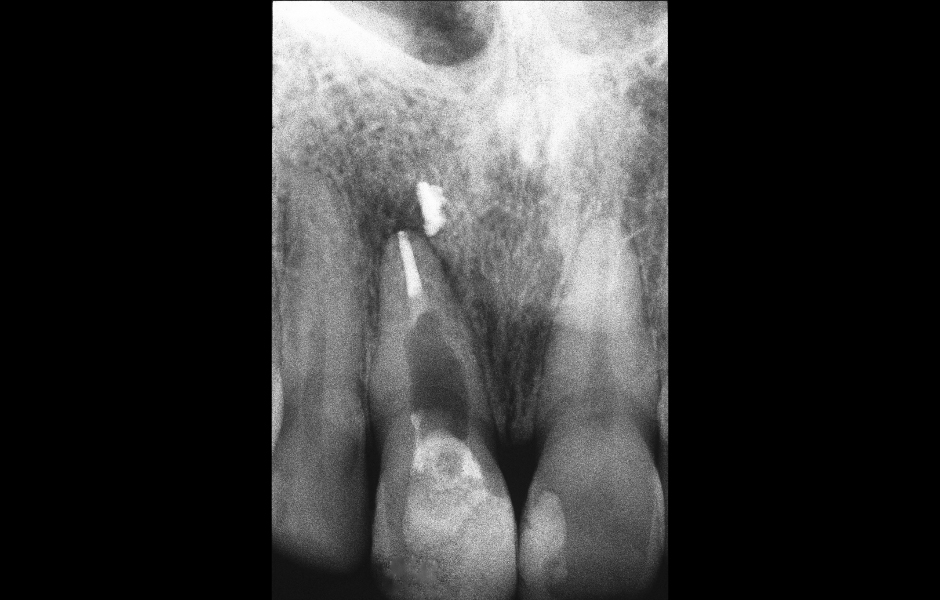

Obr. 1.1: Předoperační rentgenový snímek horního pravého středního řezáku.

Obr. 2.1: Předoperační rentgenový snímek horního pravého druhého moláru. Je patrná drobná laterální radiolucence indikující přítomnost laterálního kanálku.

Obr. 4.1: Předoperační snímek horního levého prvního moláru. Oba kanálky mesiobukálního kořene byly kompletně kalcifikované a nebylo možné je ortográdně zprůchodnit.